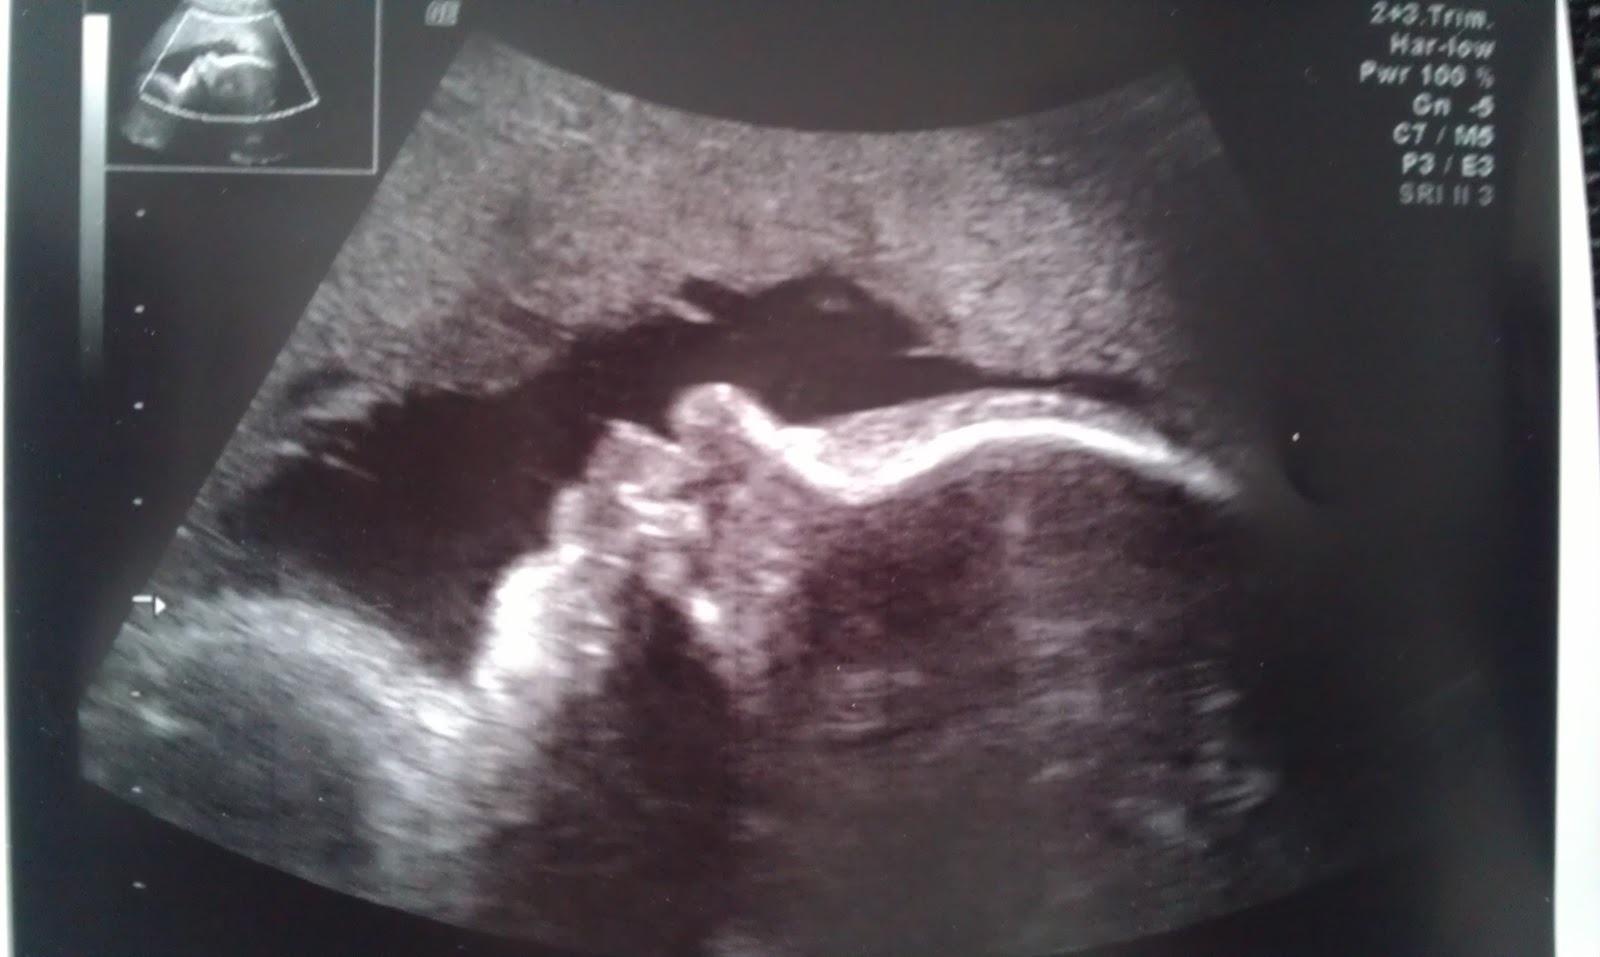

Babyen vår er, tro det eller ei, verdens fineste baby! Tenk det da, så heldig vi var å få verdens fineste! :D Haha. Det føles sånn. Et svart/hvitt bilde fra ultralyden i dag bekrefter det jeg sier. De kommer nok neppe finere enn det der. Huff, disse morsfølelsene!

Jeg var da altså på ultralyd i dag for å finne ut om morkaka hadde flyttet på seg og om jenta vår kan komme ut på normalt vis. Siden Einar ikke kunne gå fra jobben, tok jeg med meg søstra hans. Jeg har vært litt spent på denne timen, for jeg var så redd de ikke skulle gi meg et klart og tydlig svar. Så meget mørkt på å gå og vente på fødsel og lure på om det ville være trygt for meg og mini. Men, morkaka har trekt seg opp, mini ligger med hodet nedover og alt er bare velstand :) Jordmor målte også hode, magen og lårbeinet - babyen er gjennomsnitlig i kroppen og hodet er bittelitte under snittet. Det var helt som det skulle være sa jordmor, ingenting å tenke på. 1700 gram veier hun nå. For et NUSK! Dessuten klarte jordmor å fange et helt supert profilbildet av henne, og det fikk jeg med hjem. Nå som hun er blitt så stor, begynner ansiktstrekkene å bli mye klarere. Det er helt tydelig at nesa si har hun etter tante Elisabeth, søstra som var med på ultralyden :) Stor stas for en stolt tante! :) Hihi. Begge tantebarna mine har jo samme nese som mora, så det er litt moro at dette blir en søskenbarn likhet. Panna har hun nok etter sin far, mens overleppa helt klart er fra meg. Så merkelig å se! Jeg gleder meg så masse til å se henne!

Se den runde nesa da! Hihi. Sånn nese har hverken jeg eller Einar! Og den trutmunnen... Jeg må le, hun ser jo litt komisk ut. Føler nesten vi gjør noe galt når vi sniktitter på henne inni magen, hun aner jo ikke at vi er der og innvaderer. Tar bilder og analyserer og ler. Stakkar lita.

I morgen går vi faktisk inn i siste dag av september! Jeg er under to måneder til termin, og det er helt sprøtt! Om 9,5 uke er jeg mamma. Mer på overtid enn det får jeg ikke gå. Det kommer til å bli STAS! Har dere forresten sett at om ultralydbildet av babyen snues 90 grader mot venstre, så dere får det på høykant, så ser hun ut som Homer Simpson? Haha. Jeg dauer! Håper da inderlig ikke det er tilfelle når hun kommer ut. Haha. Huff.... Da må det tas en revurdering tror jeg ;)